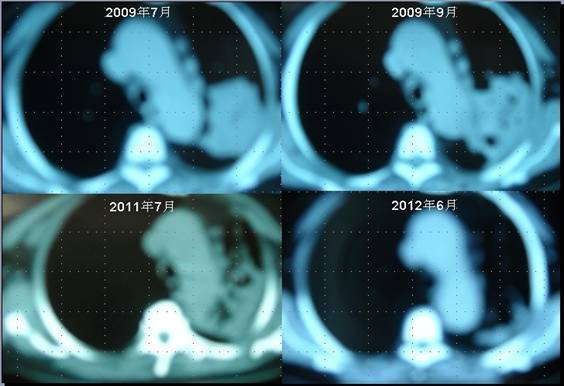

患者李某某,女,64歲,于2009年6月因咳嗽、喘憋、痰中帶血,經CT及病理等相關檢查確診為右肺上葉粘液腺癌,縱膈淋巴結轉移, 左胸膜轉移,胸腔積液,因病情及體質的原因無法接受手術及放化療等殺傷性治療,采用“中醫調胃、強腎、止血、化巖法”先后共治療8個月,現患者已有質量的存活近3年。目前隨訪患者飲食、睡眠、體力均好,可獨立完成日常家務,如今患者已經67歲。

肺癌病人李XX采用“董氏治癌法”治療前后CT變化